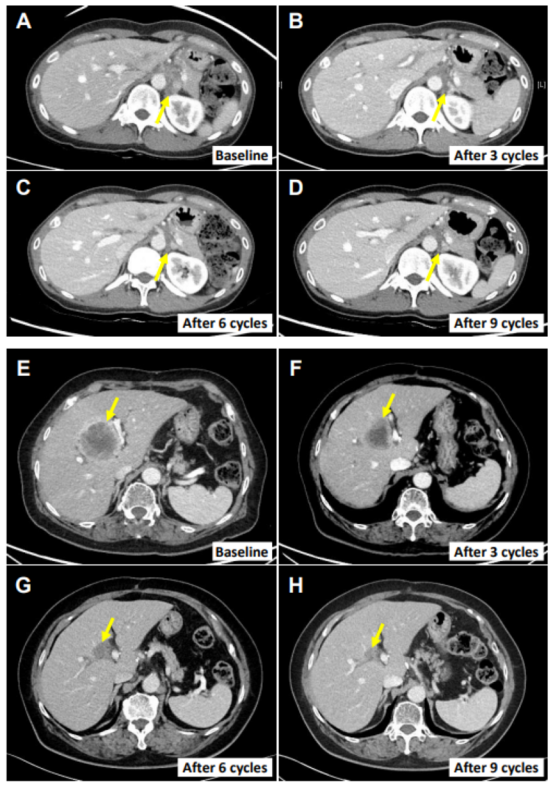

值得注意的是,患者E0107為一例40歲女性,因膽囊炎行膽囊切除術(shù),術(shù)后病理確診為膽囊癌合并腹膜癌。其病史中已包含使用吉西他濱、順鉑、5-氟尿嘧啶(5-FU)、伊立替康脂質(zhì)體及亞葉酸等多種化療藥物的治療經(jīng)歷。在采用NK細(xì)胞療法聯(lián)合帕博利珠單抗治療后,其轉(zhuǎn)移性淋巴結(jié)體積顯著縮小,減小幅度高達(dá)82.3%。

圖:其中2名患者的腫瘤消退影像情況